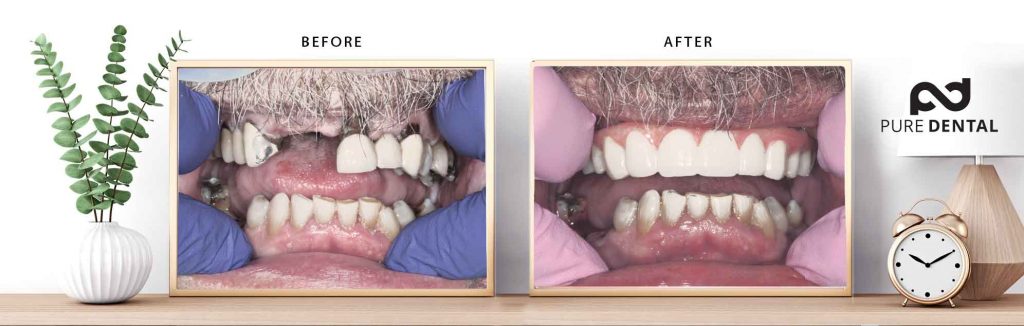

This is our own patented Four Ever Smile™ case in its temporary condition

The patient was anesthetized by a board-certified anesthesiologist and the teeth were removed and implants placed the same day. Two hours later, our lab made a temporary non-removable bridge that we screwed into place. The pictures above show the patient immediately before his teeth were removed and two hours later with a TEMPORARY bridge.

The patient was anesthetized by a board-certified anesthesiologist and the teeth were removed and implants placed the same day. Two hours later, our lab made a temporary non-removable bridge that we screwed into place. The pictures above show the patient immediately before his teeth were removed and two hours later with a TEMPORARY bridge.